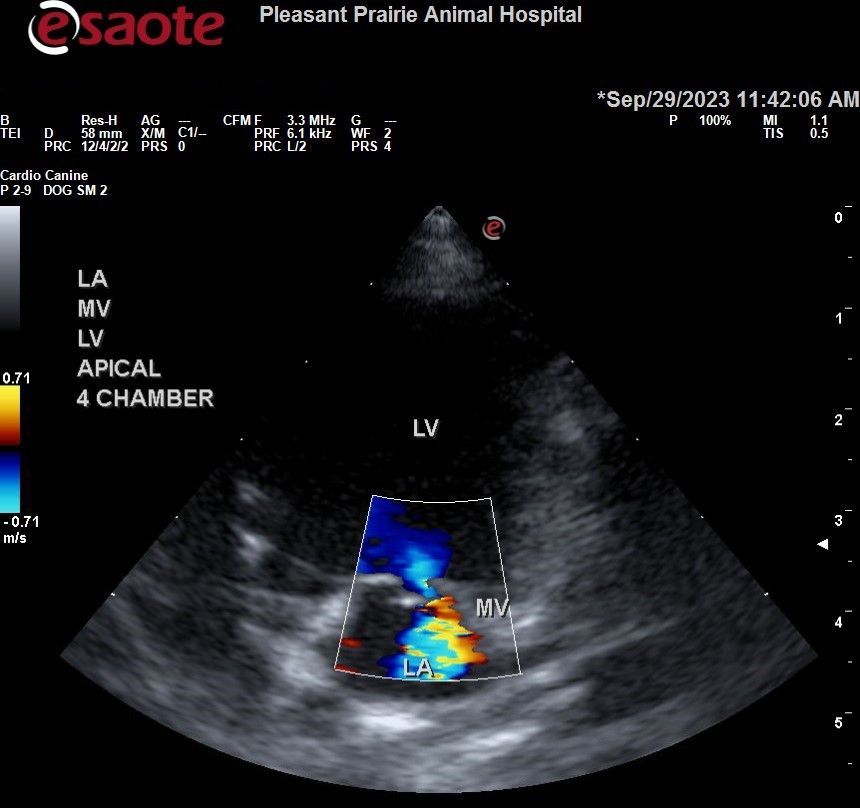

Echocardiogram (Cardiac Ultrasound)

- Used to evaluate heart size and functionality, including:

- Chamber sizes

- Valve appearance

- Identification of congenital defects